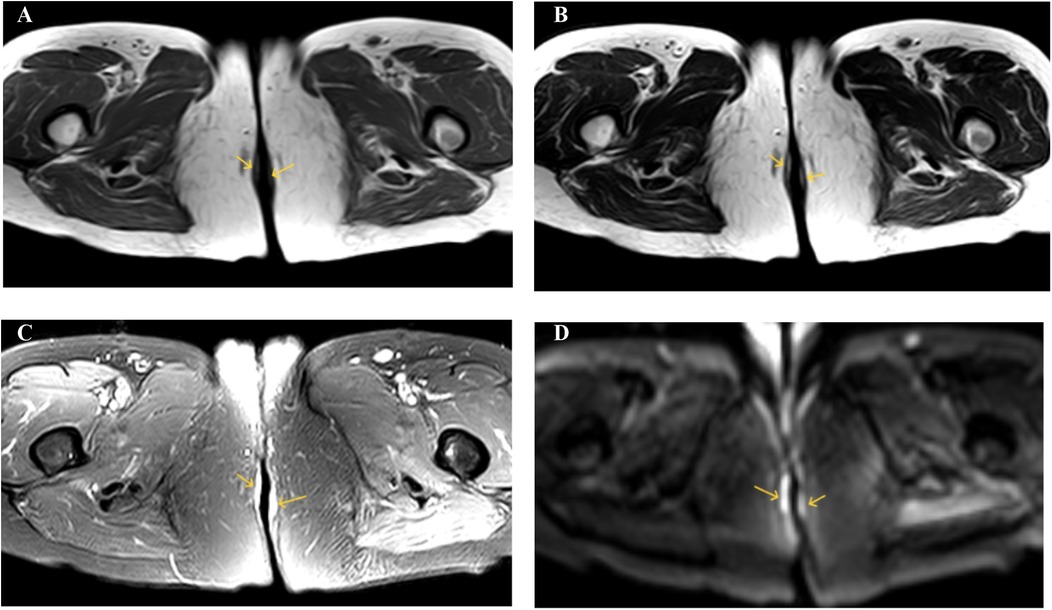

The 61-year-old female patient was admitted to the hospital due to the discovery of a perianal mass persisting for over a year, with self-reported enlargement of the lump for more than four months. The patient presented without evident clinical symptoms such as itching or scaling, with no history of specific medical conditions or prior relevant treatment. We conducted a thorough physical examination of the patients in the inpatient department, inquired about their infectious disease history, and ruled out genital warts, syphilis, and other hospitalization records. During the physical examination, bilateral perianal masses measuring approximately 3 × 3 cm were observed. These masses appeared red in color and elicited tenderness upon palpation (Figure 1A). During hospitalization, the patient underwent colonoscopy, contrast-enhanced CT of the abdomen, and contrast-enhanced Magnetic Resonance Imaging of the pelvis to rule out metastasis to other sites. Colonoscopy revealed a colonic polyp measuring approximately 0.3 × 0.4 cm, with no evidence of tumors (Supplementary Figure S1). Abdominal CT scan showed no abnormalities. The lesion in the pelvic MRI appears as low signal on T1-weighted imaging, high signal on T2-weighted imaging and diffusion-weighted imaging, and demonstrates significant enhancement (Figure 2). When tumor markers fall within normal ranges and are combined with immunohistochemistry results, other neoplastic conditions are ruled out, confirming the patient's primary PPD.

Figure 2. (A) T1WI shows low signal intensity. (B) T2WI shows high signal intensity. (C) SPAIR shows high signal intensity. (D) DWI shows high signal intensity.